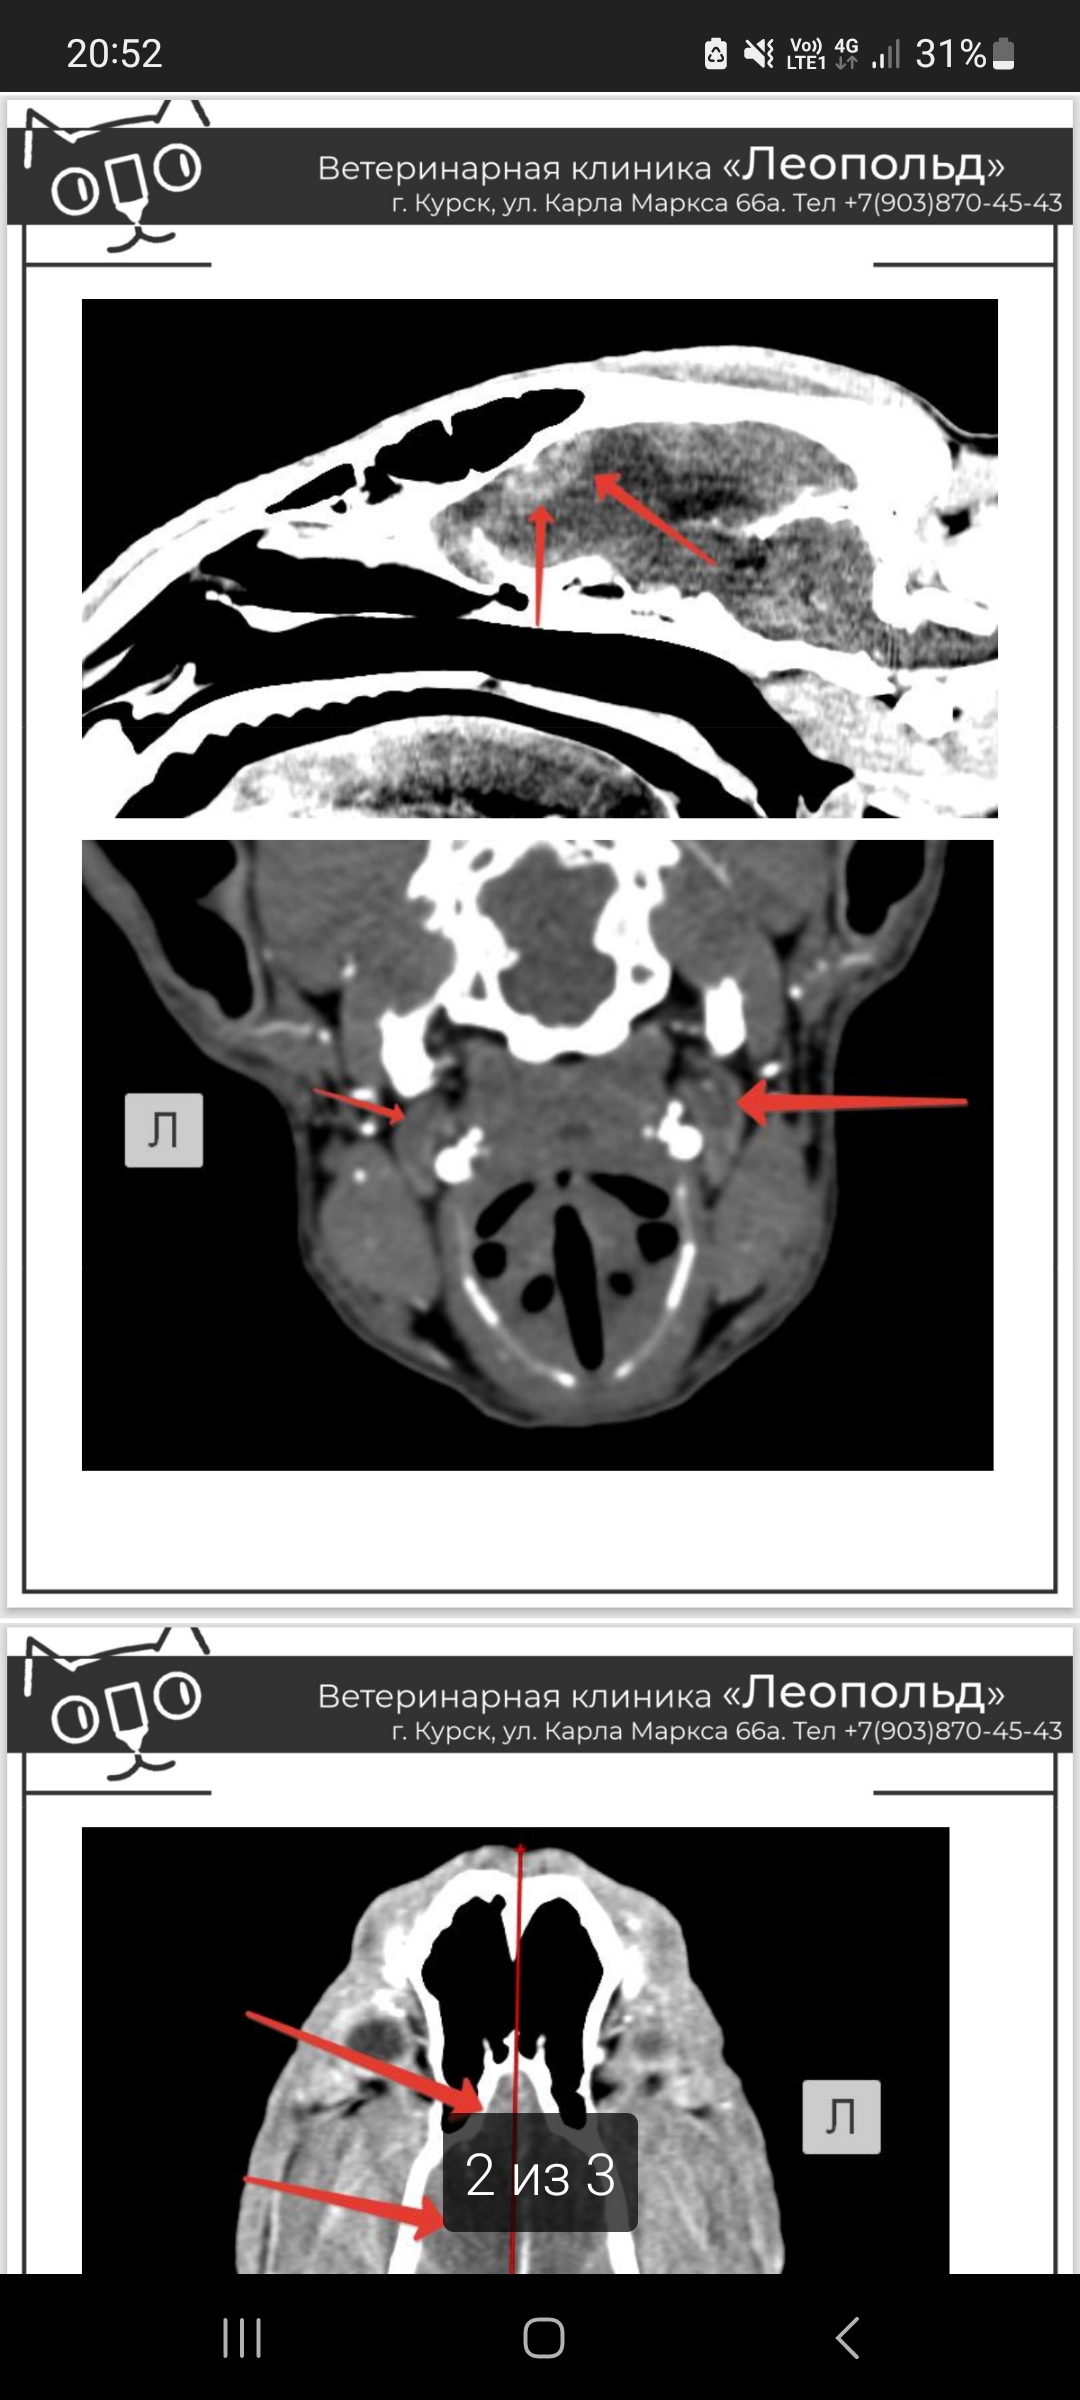

25 января у собаки случилось 4 эпилептических приступа через каждый час, срочно выехали в клинику, где нам оказали экстренную помощь. Далее мы делали обследование (анализы, кт, скрининг сердца) по которому невролог нам советует делать оперативное вмешательство. Принимаем паглюферал 3 два раза в день по одной таблетке. В ночь с 4 на 5 февраля собака стала скулить и беспокойно себя вести. В связи с чем не знаю (в период приступов выяснилась ложная щенность). Скажите можно ли как-то медикаментозно поддерживать собаку? Порода бультерьер, 9 лет. Анализы и результаты прилагаю.